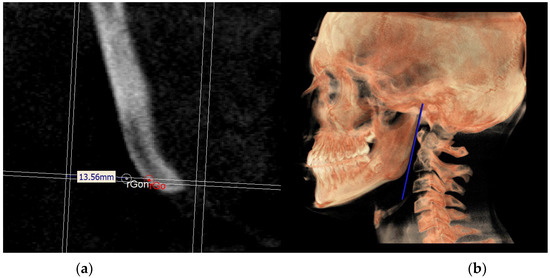

- The mandibular ramus plane (MR) (Figure 5) was identified by the following points: the middle points between the right and left condylion (mCo) and the right Gonion (rGo) and left Gonion (lGo). To adequately locate the mCo, it is advisable to draw a line on the frontal view from the right condylion to the left one to have a reference along which measure the mid-distance;